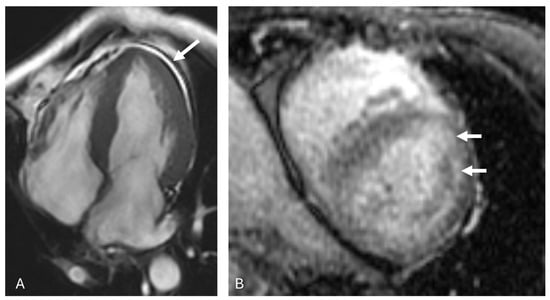

3.2. AL Amyloidosis

| AL Amyloidosis |